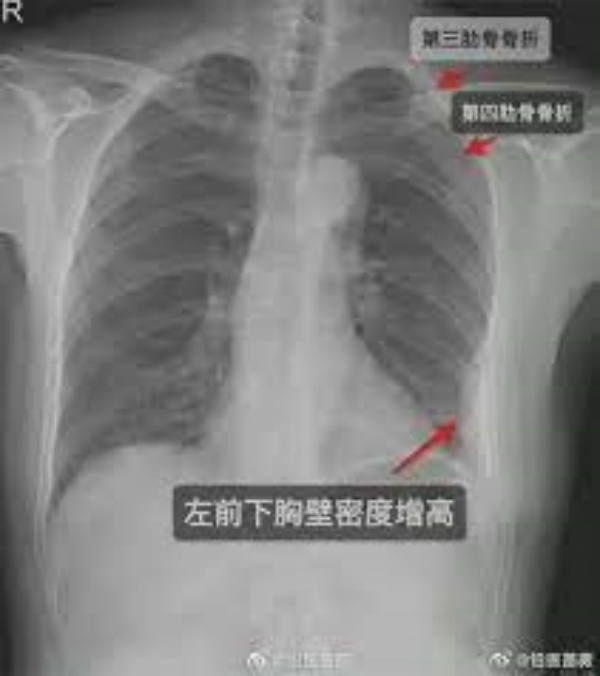

மருத்துவர்கள் அவரை பரிசோதனை செய்து எக்ஸ்ரே எடுத்து பார்த்த போது அந்த பெண்ணின் விலா எலும்பின் வலது பக்கம் 2 எலும்புகளும், இடது பக்கம் ஒரு எலும்பும் என மூன்று விலா எலும்புகள் உடைந்து இருப்பது தெரியவந்தது. இதனை அடுத்து அந்த எலும்புகளை ஒன்று சேர்க்க மருத்துவர்கள் சிகிச்சை அளித்தனர்.